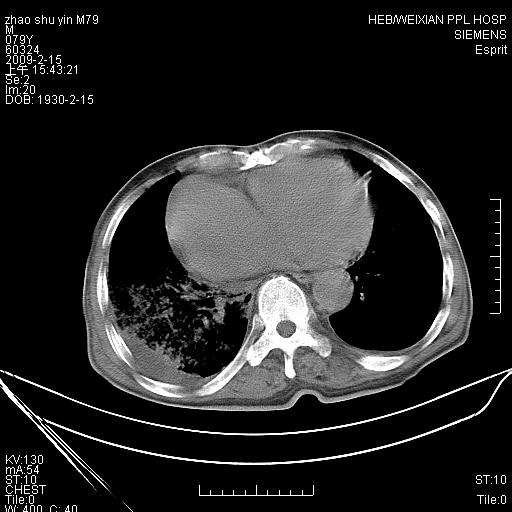

标题: CT18303:M79Y,右下肺病变

主因高热、寒战4天,伴有咳嗽,腹痛。

1。右下肺磨玻璃及蜂窝影考虑炎症 建议抗炎治疗后复查

2。右侧胸膜增厚 、右侧包裹性积液

3。心影增大 ,左心房增大为甚

4。右下肺门饱满(肿大淋巴结)